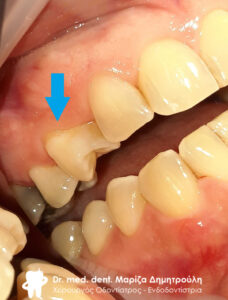

Σπασμένο δόντι

Ο ασθενής έσπασε το δόντι του κατά τη διάρκεια του γεύματος του. Το δόντι ήταν απονευρωμένο και δυστυχώς ο ασθενής καθυστερούσε την κάλυψη και προστασία του δοντιού με θήκη / στεφάνη δοντιού. Αυτό είχε ως αποτέλεσμα το δόντι μετά από κάποιο χρονικό διάστημα να σπάσει και να πρέπει να εξαχθεί από το στόμα το ασθενή. Αν το δόντι είχε προστατευτεί με θήκη, το δόντι θα μπορούσε να είχε σωθεί και ο ασθενής δε θα έχανε το δόντι του.

Τα απονευρωμένα δόντια είναι επιρρεπή στα κατάγματα και γι΄ αυτό το λόγο, είναι σημαντικό να προστατεύονται με θήκη δοντιού, ώστε να μπορούν να διατηρούνται άφοβα μέσα στο στόμα. Αυτό οφείλεται